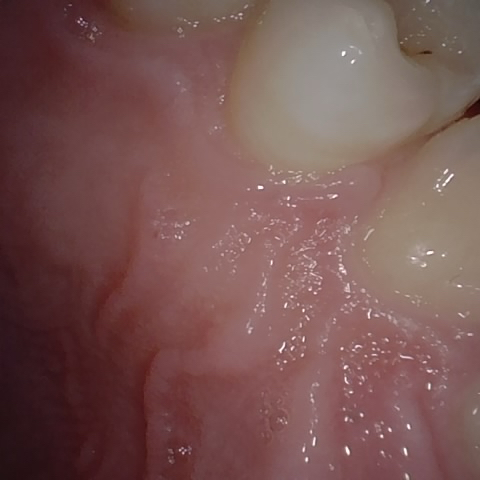

Annotated as "Good"